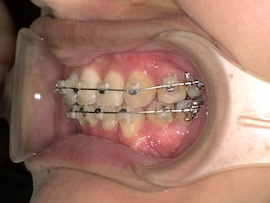

そして1ヶ月後、

牽引のため内側の装置が新しくなりましたが、これがびっくりするくらい話しづらいです…。

元々装置はついていたので案外大丈夫かと思っていたのですが、想像以上の違和感でした。

また、異物を感じているのか明らかに唾液の量が増えた気がします。(笑)

慣れるのかどうか本当に不安で先生にも「完全には慣れないかもしれない」と言われたものの、1週間くらいすれば気にならない程度には慣れました。口の中ってすごいですね。(笑)